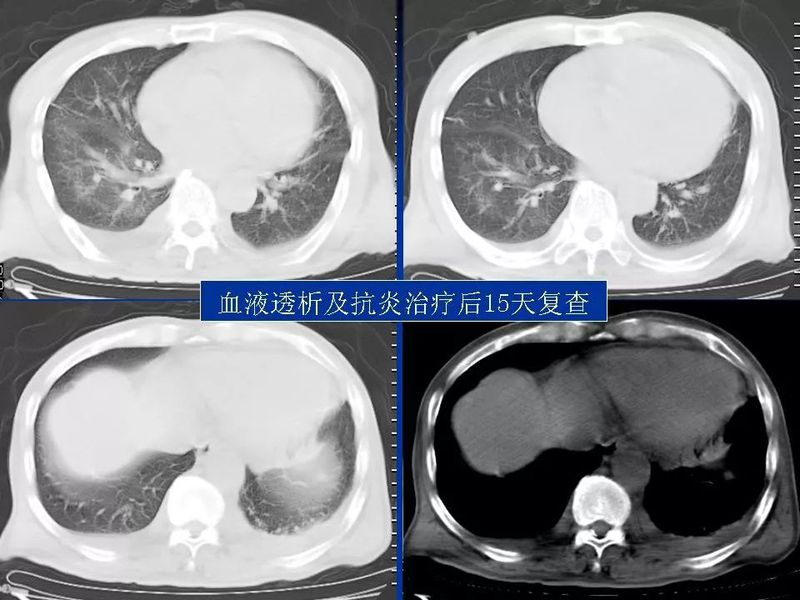

主任提醒:这个病很容易误诊为肺炎!